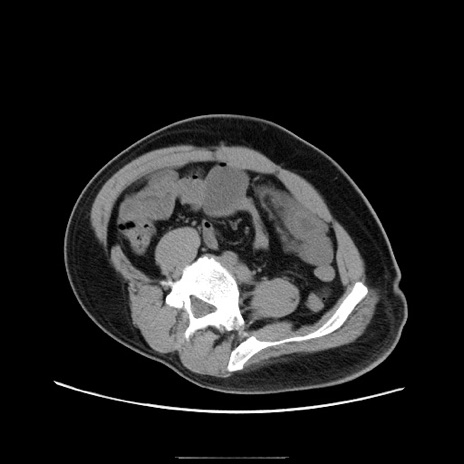

症例22(横断像)

【症例】50歳代男性

【主訴】腹痛

【現病歴】AVMからの被殻出血のため回復期リハ病棟入院中。 本日午後3時頃急に下腹部痛が出現した。

【既往歴】AVM、被殻出血、虫垂炎、高血圧

【身体所見】意識晴明、左半身不全麻痺、会話の理解は良好、36.5°C、腹部:膨隆、全体に板状硬、下腹部正中に圧痛点あり、反跳痛-、筋性防御不明、右下腹部にope scar

【データ】WBC 9400、CRP 0.06